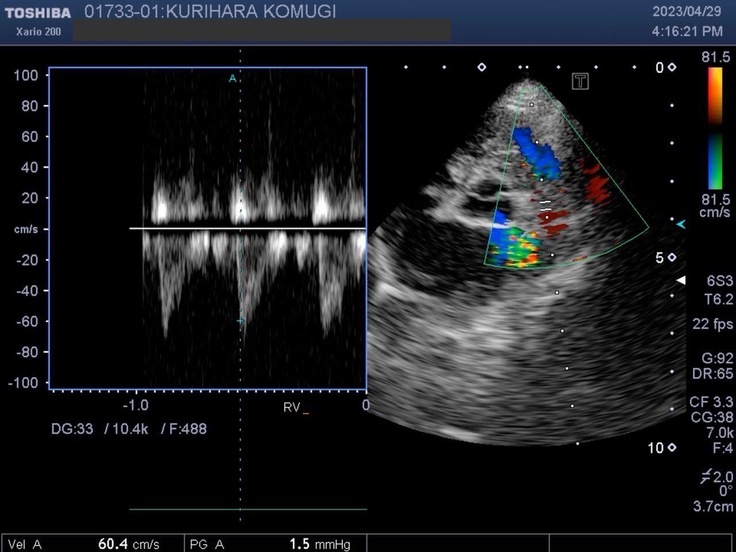

▽エコー写真

※かかりつけの動物病院からの掲載許可をいただいています。

※循環器専門病院からの掲載許可をいただいています